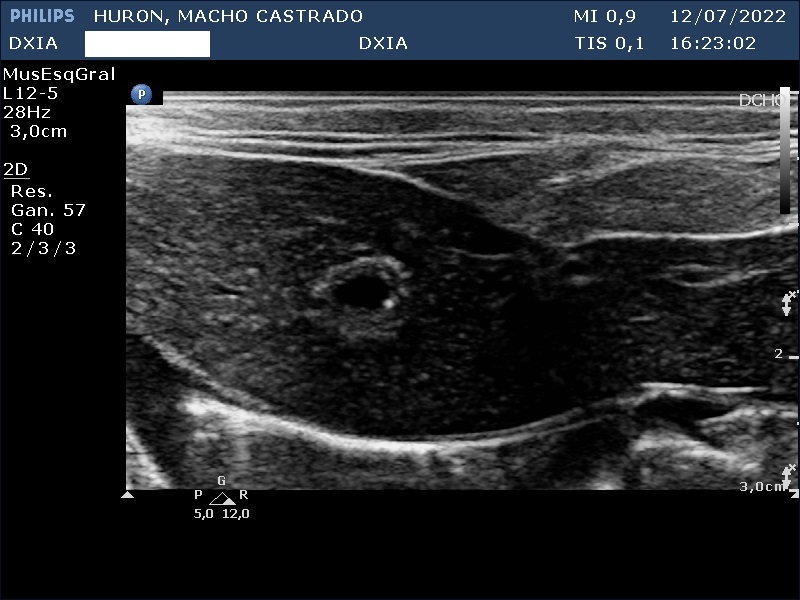

Hallazgos ecográficos